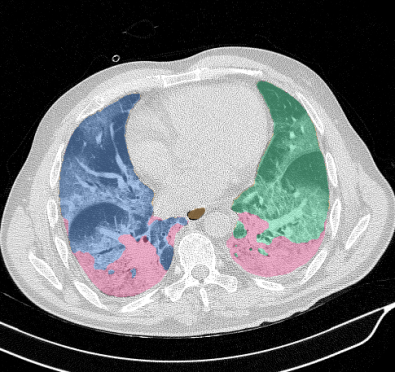

Lobar segmentation results for the proposed method and PTK are shown in Figure 5 for right lungs and Figure 6 for left lungs. For each image in the COVID-19 dataset (133 images in total), the lobar segmentation result was used to extract the amount of poor aeration () and consolidation () in each lobe. Common phenotypes of COVID-19 affected lungs were identified by hierarchical clustering over the fraction of poorly aerated and consolidated tissue in each lobe. Dendrographic analysis in Figure 7 reveals four primary clusters of patients that were identified by the hierarchical clustering: (a) mild loss of aeration primarily in the two lower lobes without consolidation; (b) moderate loss of aeration focused in the two lower lobes with or without consolidation in lower lobes; (c) severe loss of aeration throughout all lobes with or without consolidation; and (d) severe loss of aeration and consolidation throughout all lobes.

Lung segmentation results for the polymorphic and nonpolymorphic models are shown in Figure 3. Quantitative evaluation of lung segmentations was performed on CT images by comparing the segmentations to ground truth manual segmentations. The Dice coefficient was used to measure volume overlap and the average symmetric surface distance (ASSD) was used to assess boundary accuracy. The ASSD and Dice coefficient results for each of the four evaluation datasets are shown in Table 2. Overall, on the COVID-19 dataset the polymorphic model achieved an average ASSD of mm and average Dice coefficient of . By comparison, the nonpolymorphic model achieved an average ASSD of mm and average Dice coefficient of . ASSD and Dice coefficient results with respect to nonaerated lung volume fraction are displayed in Figure 4. Two-way analysis of variance revealed a significant interaction between model and nonaerated fraction for each evaluation metric, indicating that the regression coefficients with respect to nonaerated fraction were significantly different for polymorphic vs. nonpolymorphic models.